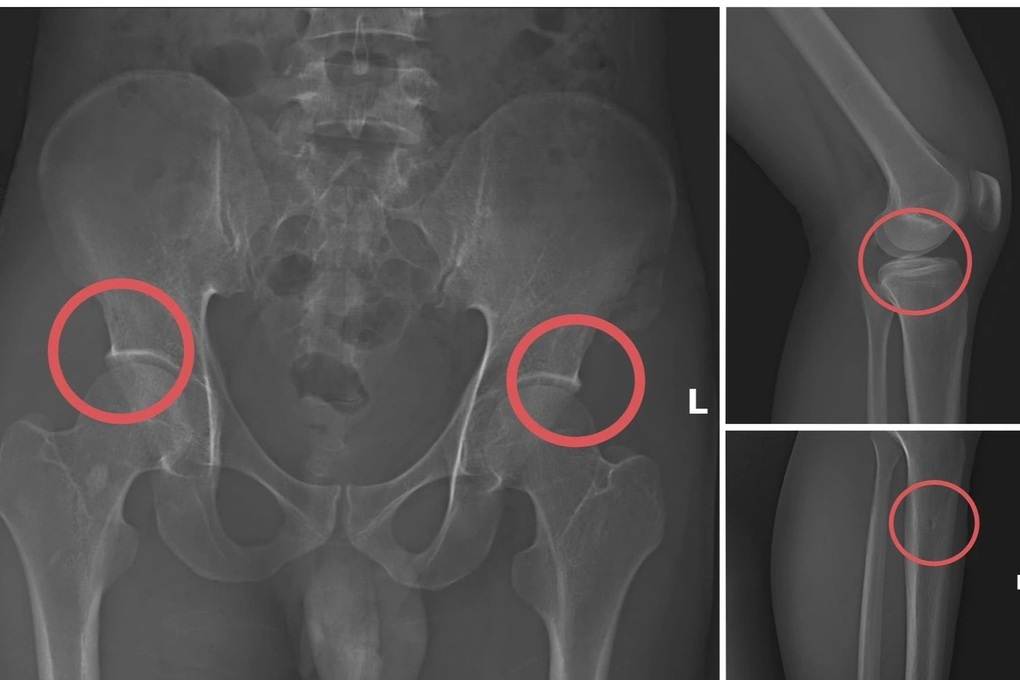

Một số tổn thương xương do các đối tượng tạo ra nhằm trục lợi bảo hiểm nhân thọ (Ảnh phim chụp XQ, Công an Phú Thọ cung cấp).